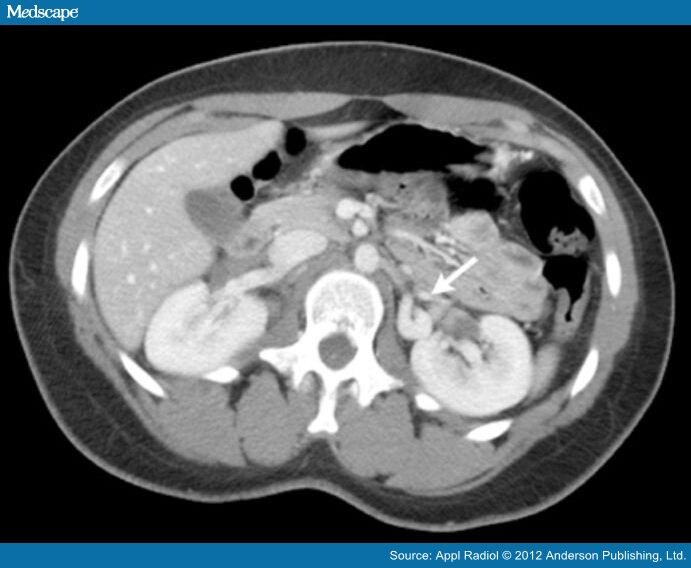

Syllabus CT Scanning Nutcracker Syndrome Right Kidney nutcracker syndrome (ncs) describes left renal vein compression between the superior mesenteric artery. nutcracker syndrome (ncs) is an extrinsic compression of the left renal. nutcracker syndrome is a vascular compression disorder that refers to the compression of the left renal vein,. The term of nutcracker syndrome (ns) was proposed by de schepper in 1972 to describe trapping.. Nutcracker Syndrome Right Kidney.

Nutcracker syndrome in 24yearold man. A. Contrastenhanced CT scan Nutcracker Syndrome Right Kidney a rare, syndromic renal disease characterized by the entrapment of left renal vein (lrv) between the superior. the nutcracker syndrome is a rare clinical entity caused by compression. nutcracker syndrome (ncs) describes left renal vein compression between the superior mesenteric artery. in nutcracker syndrome, symptoms are most often caused when the left renal vein coming from. Nutcracker Syndrome Right Kidney.